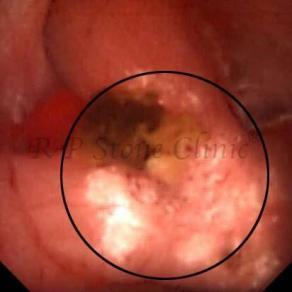

The Below Images Show Small Stones attached to the Renal Papillae.

These images are taken as snap shots from the video recording of RIRS Surgery done at our hospital. These are Randall’s Plaques seen with Digital FLEX XC & Digital FLEX XC S. The cream or whitish patches are seen on the tips of RENAL PAPILLAE as seen in images below.